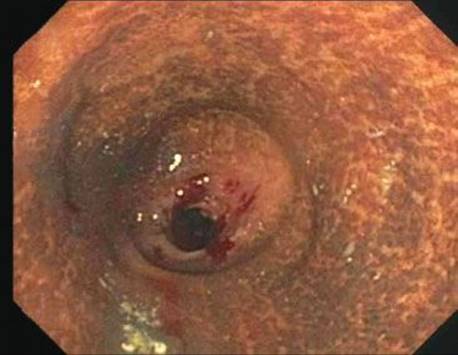

Melanosis coli refers to coarse, brown-black pigment in the cytoplasm of the colon’s resident macrophages. Despite the name, ultrastructural studies demonstrated the pigment is lipofuscin, not melanin (this particular factoid is a favorite among those who write test questions!).111 The pigment is derived from stimulant laxatives containing senna, aloe-emodin, chrysophanol, cascara, frangula, and rhein.112 The purgative effects of such preparations stem from their ability to increase colonic motility and decrease colonic absorption, resulting in decreased transit time and softer stools. The endoscopic images in patients with melanosis coli can be impressive (Fig. 4.231). Any region of the colon can be affected with no consistent regional pattern of involvement: some claim the distal colon is most affected, while others found the changes most pronounced proximally.113,114 Melanosis coli is seen in up to 73% of patients with chronic laxative usage and in up to 6% of biopsy and autopsy cases.115,116 Such findings have been documented within 4 months of regular laxative usage and the findings reverse 6 to 11 months following cessation (Figs. 4.232–4.238).117,118 Early literature suggested anthracoid laxatives were a risk factor for colonic neoplasia based on provocative animal and human studies showing an increased association of melanosis coli in patients with adenomas and carcinomas.119,120 Today, this theory has been abandoned.121,122

Figure 4.231 Melanosis coli, endoscopic image. This endoscopic image shows striking mucosal pigment deposition. This patient had a 10-year history of senna intake for chronic constipation.